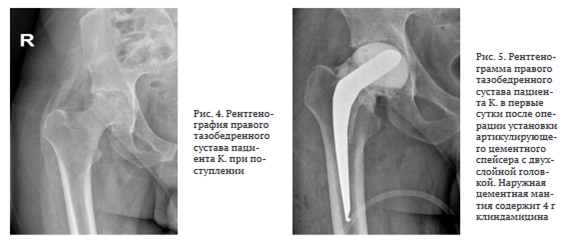

Антибактериальную терапию на амбулаторном этапе не получал. Поступил в НМИЦ ФПИ с жалобами на боль в левом тазобедренном суставе, передвигался при помощи костылей. Функциональные показатели сустава по шкале HHS — 35, по шкале WOMAC — 79, выраженность болевого синдрома по шкале ВАШ — 7 баллов. На КТ левого тазобедренного сустава определена деструкция верхнего фрагмента головки левой бедренной кости без признаков контактной деструкции вертлужной впадины, сужение суставной щели (рис. 1).

На рентгенограмме правого тазобедренного сустава визуализировали контактную деструкцию суставных концов, сужение суставной щели (рис. 4).